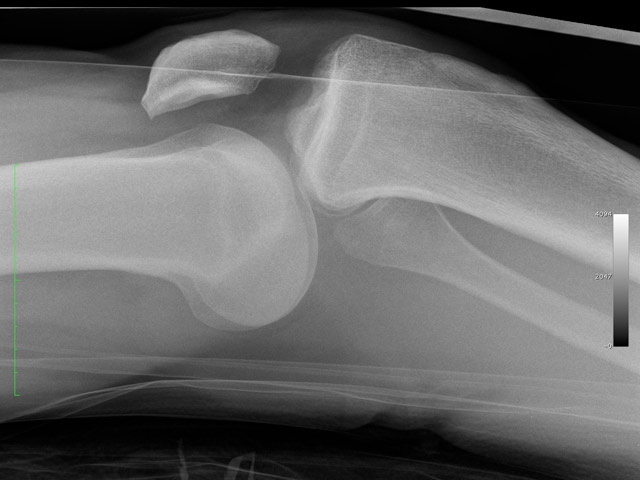

Anterior dislocation